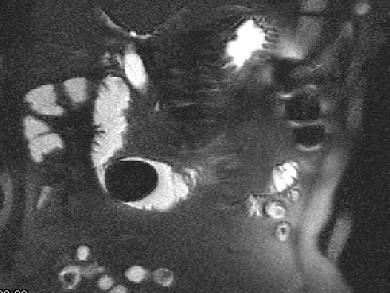

问题 女 ,80岁 ,右上腹疼痛反复发作 6个月,加重 2天 ,曾有胆囊炎及胆结石病史,影像检查如图,应诊断为 ( )

选项 A、十二指肠间质瘤 B、十二指肠腺瘤 C、十二指肠巨大胆结石(胆囊十二指肠瘘) D、十二指肠蛔虫 E、十二指肠息肉

答案 C